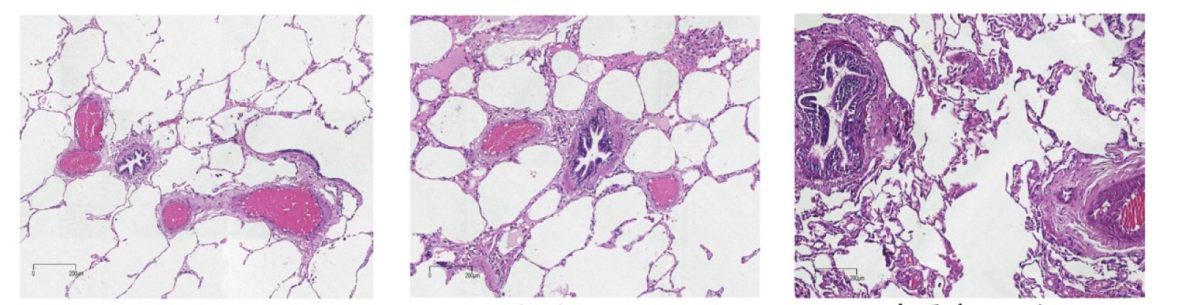

△E-mail: ZHAO Shutong, DING Yun, LI Yuechuan, ZHAO Xiaoyun, GENG Hua, XU Meilin. Pathological features of mild chronic obstructive pulmonary disease and their correlation with inflammatory factors[J]. Tianjin Medical Journal, 2024, 52(6): 643-647.